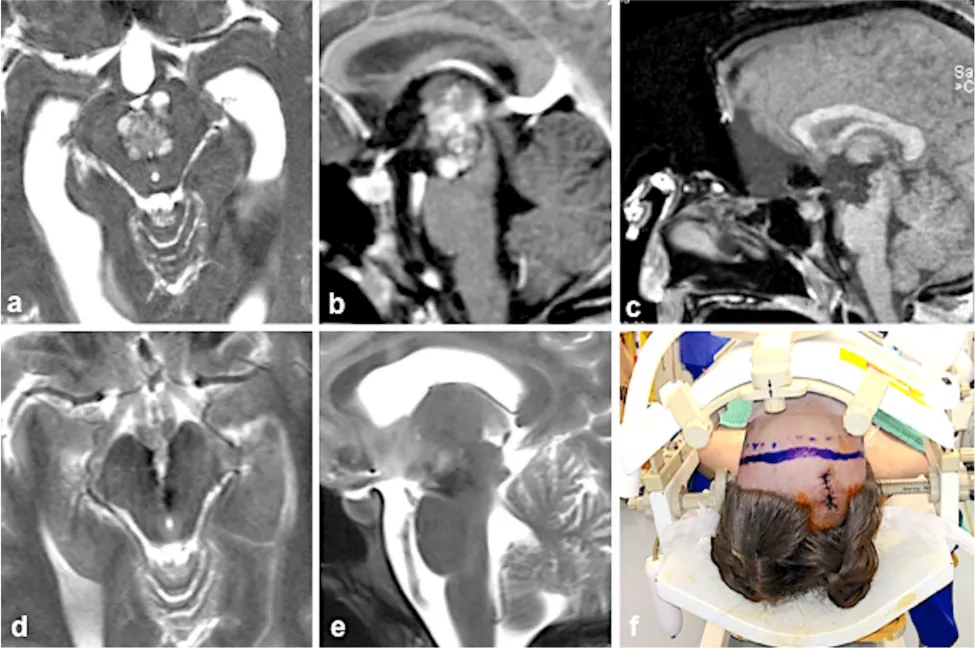

病例一:21岁女性患者,脑脊液循环通路梗阻伴神经功能异常

患者因眼球运动障碍、复视症状就诊,影像学检查提示中脑海绵状血管瘤深在性占位,且病灶向上方侵袭性生长,阻塞脑脊液正常循环通路,引发剧烈头痛、呕吐等颅内高压临床症状。

手术实施方案:采用前纵裂解剖入路,借助大脑正前方自然解剖间隙结构,精准抵达病灶区域,完成病灶完整性切除。

临床预后结果:术后眼球运动障碍出现短暂性加重,但在3个月时间内完全恢复正常,未遗留任何神经功能后遗症,患者成功回归正常社会生活。

病例二:19岁女性患者,两次出血事件后出现神经功能受损

患者病灶已发生两次破裂出血事件,临床表现为头痛、复视及右手肌力进行性下降,病灶深埋于脑干内部结构,表面未出现任何异常病理体征,手术实施难度极高。

手术实施方案:采用左外侧幕下小脑上-经天幕解剖入路,从侧后方以最小组织扰动路径,精准定位并完整切除病灶结构。

临床预后结果:术后出现短暂性眼部活动功能障碍,在数周时间内逐步改善并实现完全康复,肢体肌力得到完全保留。